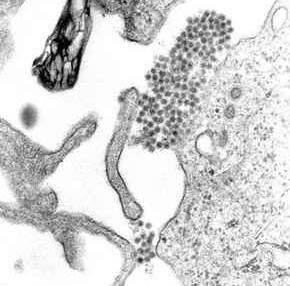

El dengue es una enfermedad viral producida por el virus del dengue (serotipos 1, 2, 3 y 4) perteneciente al género Flavivirus. Los 4 serotipos producen el dengue clínico y sus posibles complicaciones, el dengue hemorrágico y el síndrome de shock del dengue.